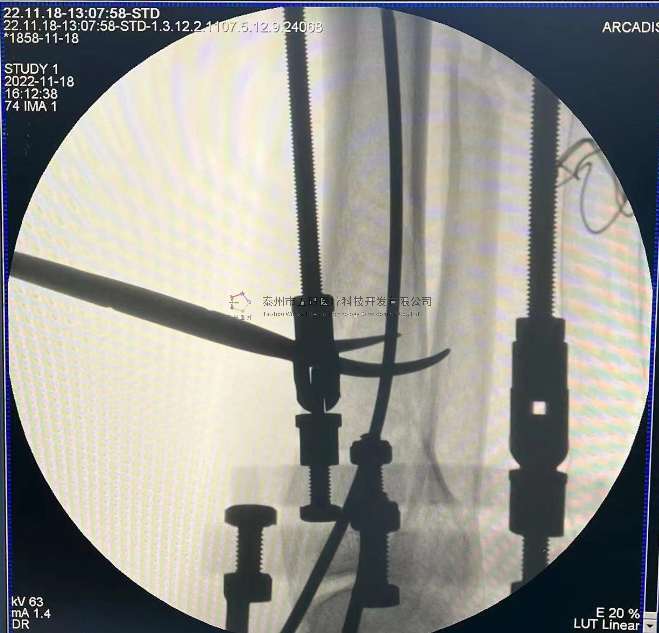

外架馬蹄環(huán)穿過(guò)骨針,更方便調(diào)整固定角度。